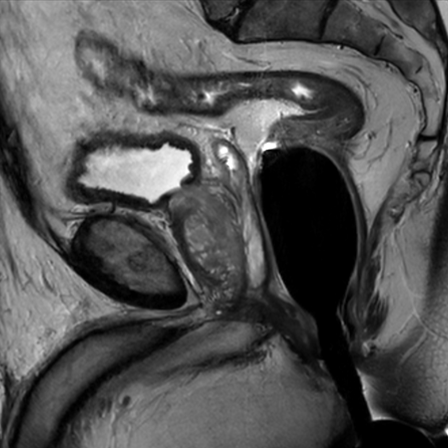

Prostate imaging with dS Endo + dS Torso coil

• Clinical Application